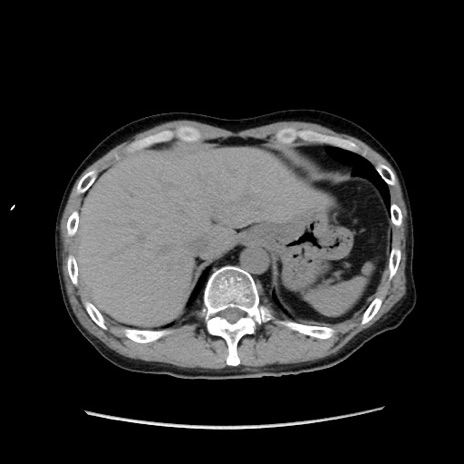

冠状断像